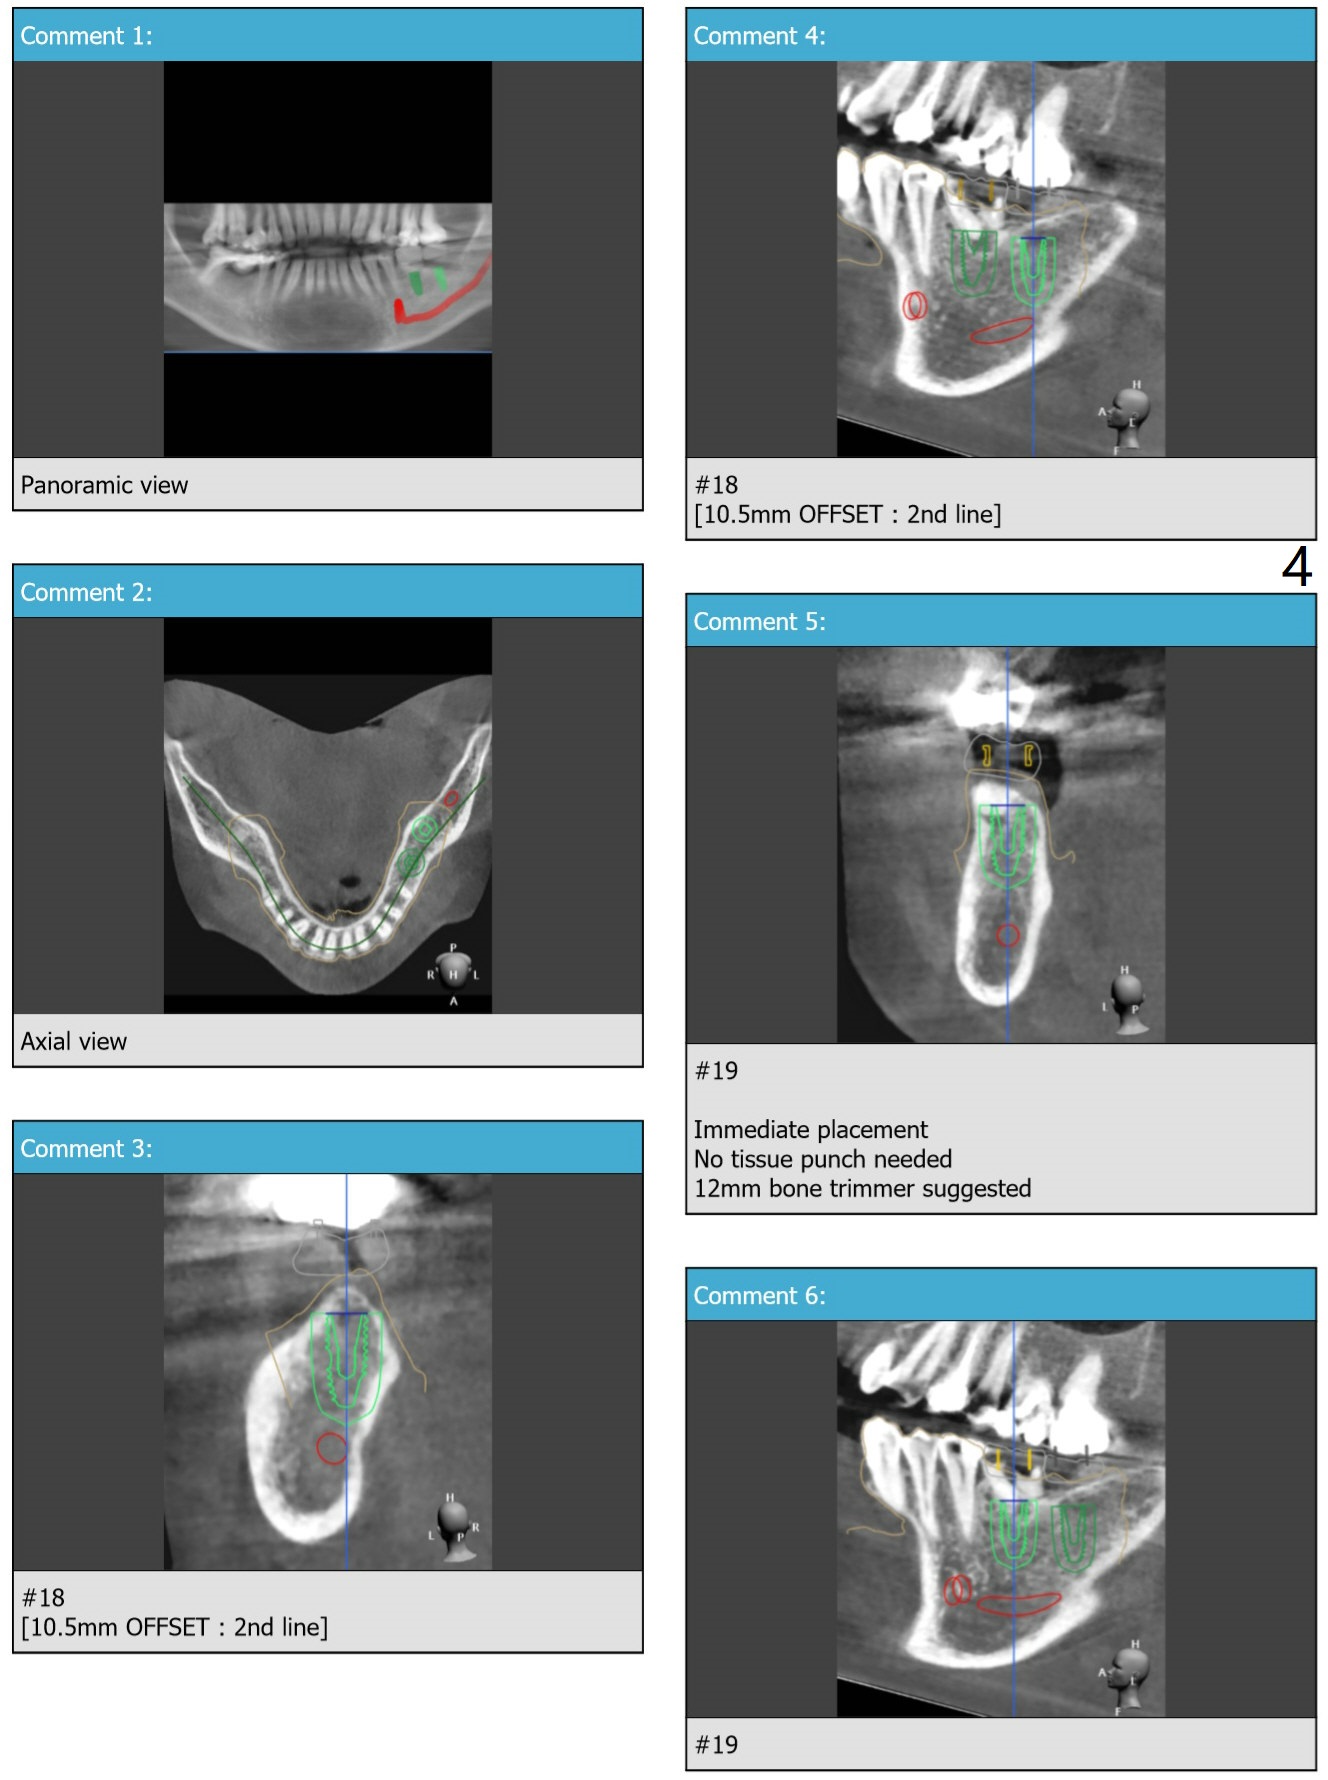

Limited Vertical Space

Return to Lower Molar Immediate Implant, Trajectory II